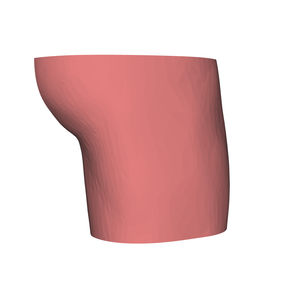

Anatomisches Modell / Schulter HUM-Efür Punktionenfür Injektionenfür Ultraschalluntersuchungen

- Körperteil

- Schulter

- Farbe

- rosa

Echogene und röntgendichte anatomische Schaufensterpuppen

für eine bessere Ausbildung in interventionellen Verfahren unter Ultraschall und Röntgenstrahlen

Identifizierung anatomischer Orientierungspunkte mit Ultraschall und Röntgenstrahlen

Training für Punktion und Infiltration unter Ultraschall und Röntgenstrahlen

Hautgetreues Stichempfinden mittels Echo und Radio

Alle unsere Schaufensterpuppen sind echogen und röntgendicht und können bis zu 600 Injektionen pro Stelle tragen.